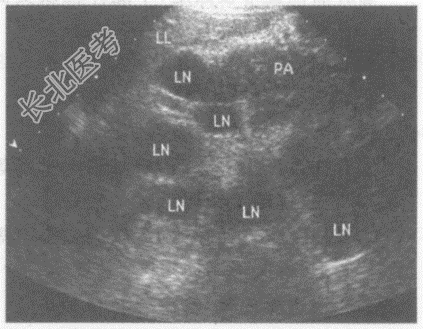

- 单项选择题临床资料:男性患者, 55岁,胃癌术后5年。

超声综合描述: 脊柱前方腹主动脉周围可见多个大小不等的类圆形低回声区,最大1.8cm×1.3cm, 长径/短径比值<2,边界尚清, 部分融合。

超声提示: A、腹膜后肿大淋巴结